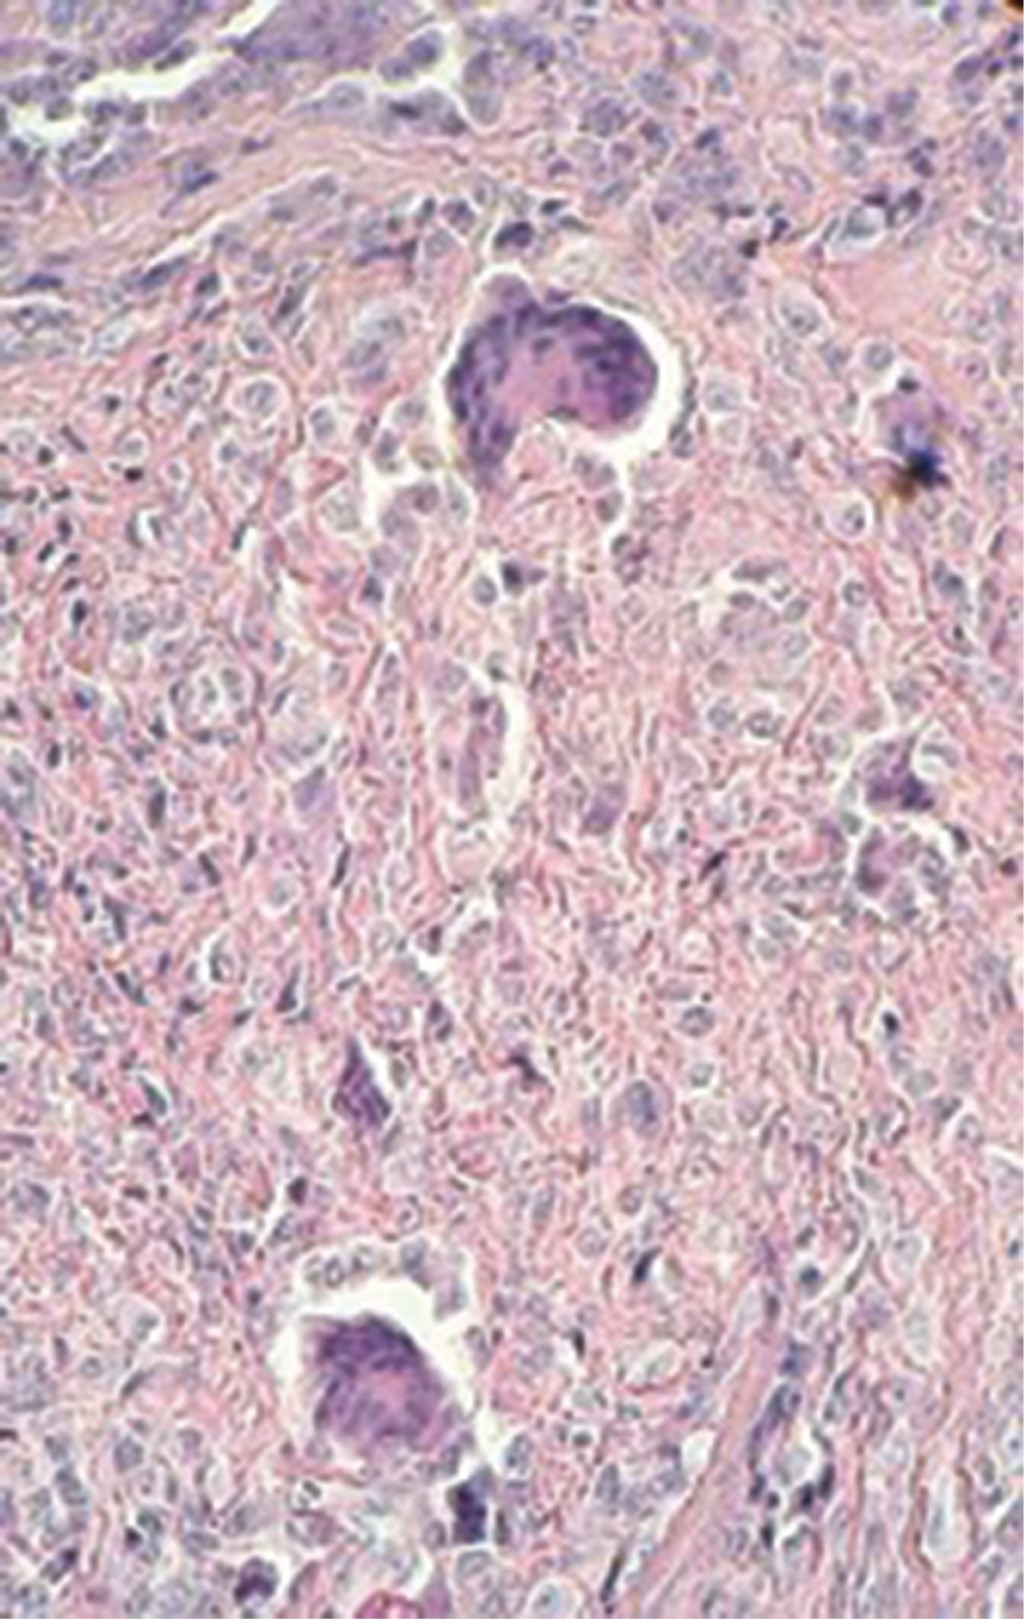

HISTOPATOLOGíA

En la histopatología del TCGVT se observan lóbulos con celularidad mixta rodeados de colágena densa. Las células del infiltrado muestran un núcleo vesiculoso con contenido lipídico, o con hemosiderina, lo cual proporciona aspecto espumoso a estas células. Además, se observan células gigantes eosinofílicas y multinucleadas, similares a los osteoclastos. Estas células contienen hasta 60 núcleos, y se forman por fusión de células mononucleares.16

Se solicita radiografía de mano derecha, en la cual se observa radiolucidez circunscrita a nivel de articulación interfalángica distal. Durante la exploración quirúrgica, al extirpar la lesión, se obtiene una neoformación de color amarillo, lobulada, de consistencia firme, superficie aperlada, de bordes bien definidos (Figura 2). Se efectúa reconstrucción mediante colgajo de avance en "L", sin complicaciones (Figura 3). En la histopatología se observa una tumoración circunscrita constituida por numerosas células de aspecto fusiforme y epitelioide que forman haces muy compactos, así como formación de numerosas células gigantes multinucleadas de tipo osteoclasto (Figura 4). El paciente evolucionó en forma favorable, con adecuada cicatrización de la herida, y sin recidivas hasta el momento (Figura 5).